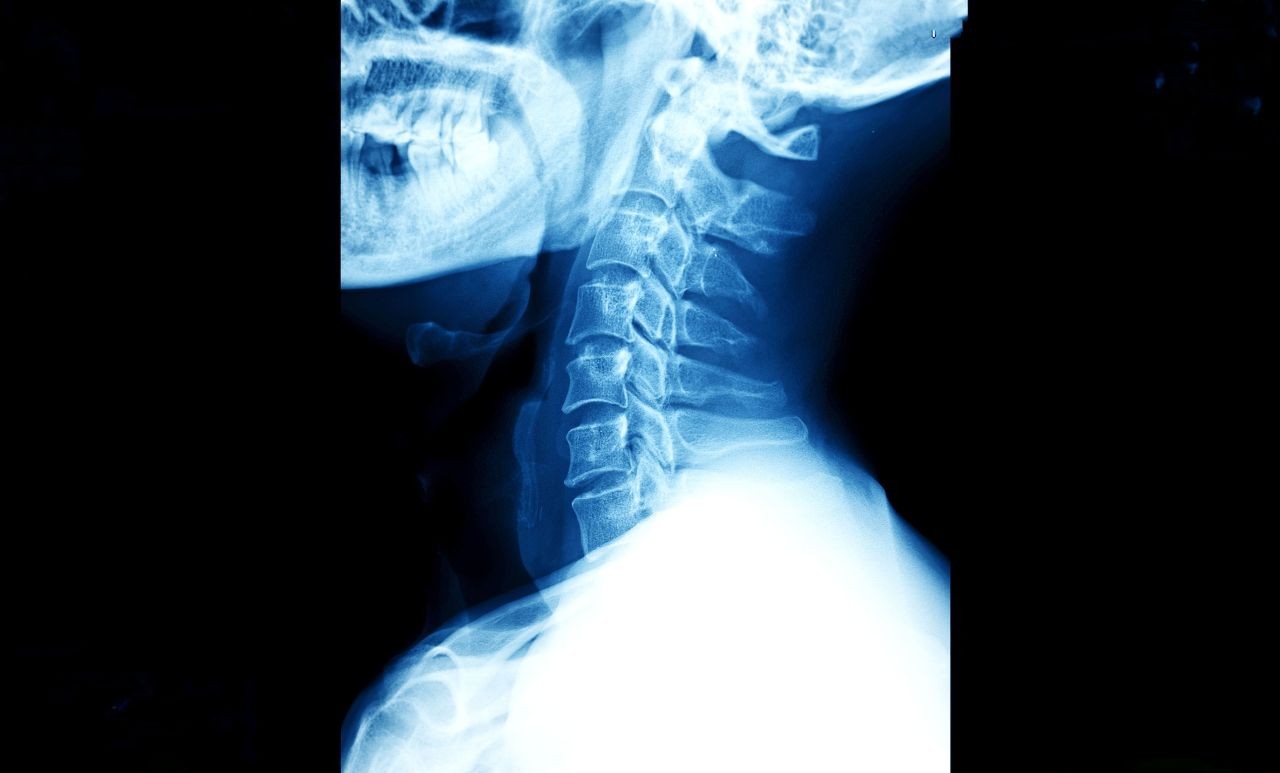

x-ray-image-of-human-neck-2026-01-07-06-59-02-utc-1

Cervical Disc Surgery: Replacement vs. Fusion for Neck Pain

If you have a herniated disc in your neck, you know the feeling: the constant ache in your neck, the electric shocks down your arm, the numbness in your fingers that makes buttoning a shirt impossible.

When physical therapy and injections stop working, surgery becomes the conversation. For decades, the "gold standard" was to fuse the bones together (ACDF). But today, active patients in New York have a better option: Artificial Disc Replacement (ADR).